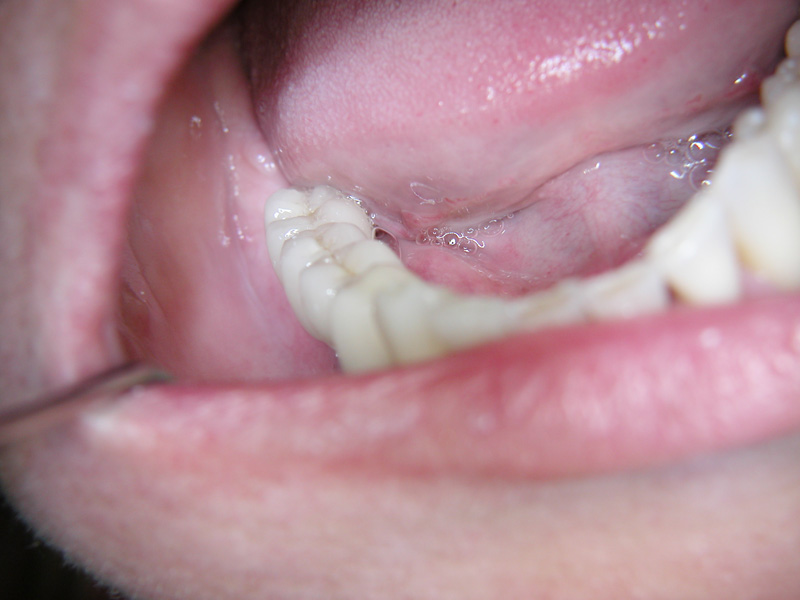

Implante - Galerie Foto

Caz III